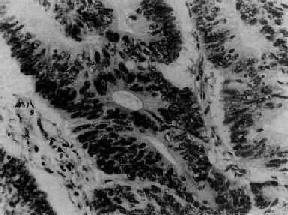

图13-18 卵巢粘液性囊腺瘤

瘤组织腺体扩大成囊,被覆囊壁的瘤细胞呈高柱状,核位于基底部,胞浆含大量粘液,(图中呈浅色透亮状)